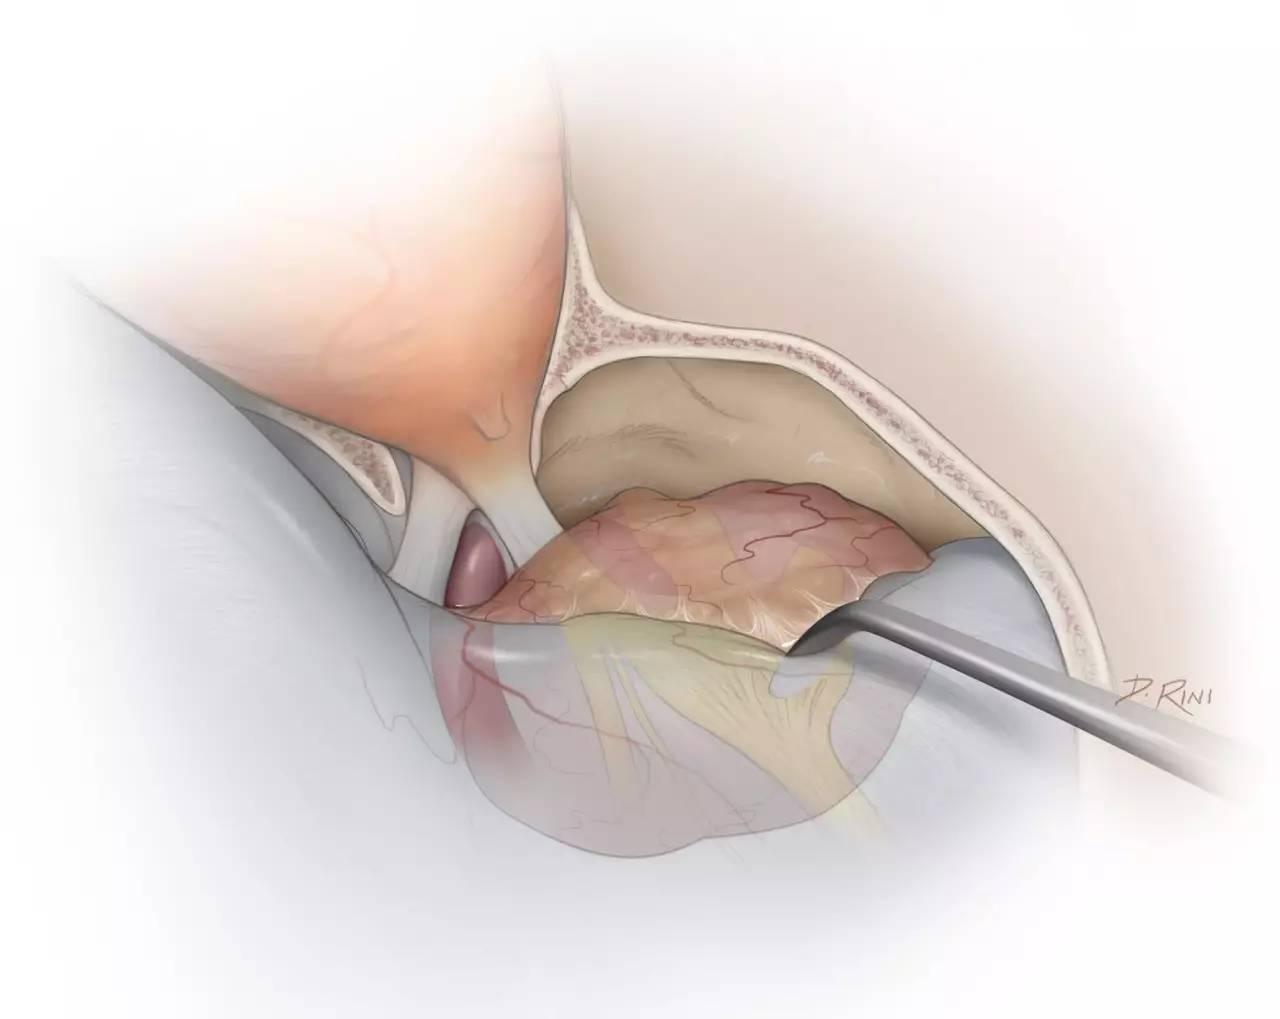

图5:完成眶颧开颅、硬膜外前床突切除术后,进一步切除颞下骨质,即可直视中颅窝底。逐渐掀起中颅窝硬膜,可见三叉神经上颌支及下颌支的硬膜袖套包绕着神经穿经中颅底,将其与颞叶硬膜的外层(中颅窝硬膜的脑膜层,译者注)相分离。该步骤即从硬膜外将海绵窦肿瘤的窦外部与窦内部相分离。

图6:在Glasscock三角内打开颈内动脉管顶壁,并置入Fogarty球囊。值得注意的是,只有在颈内动脉周围进行分离时,笔者才将球囊置入术野,而在这之前,并不提前进行该操作,以免影响其他操作。